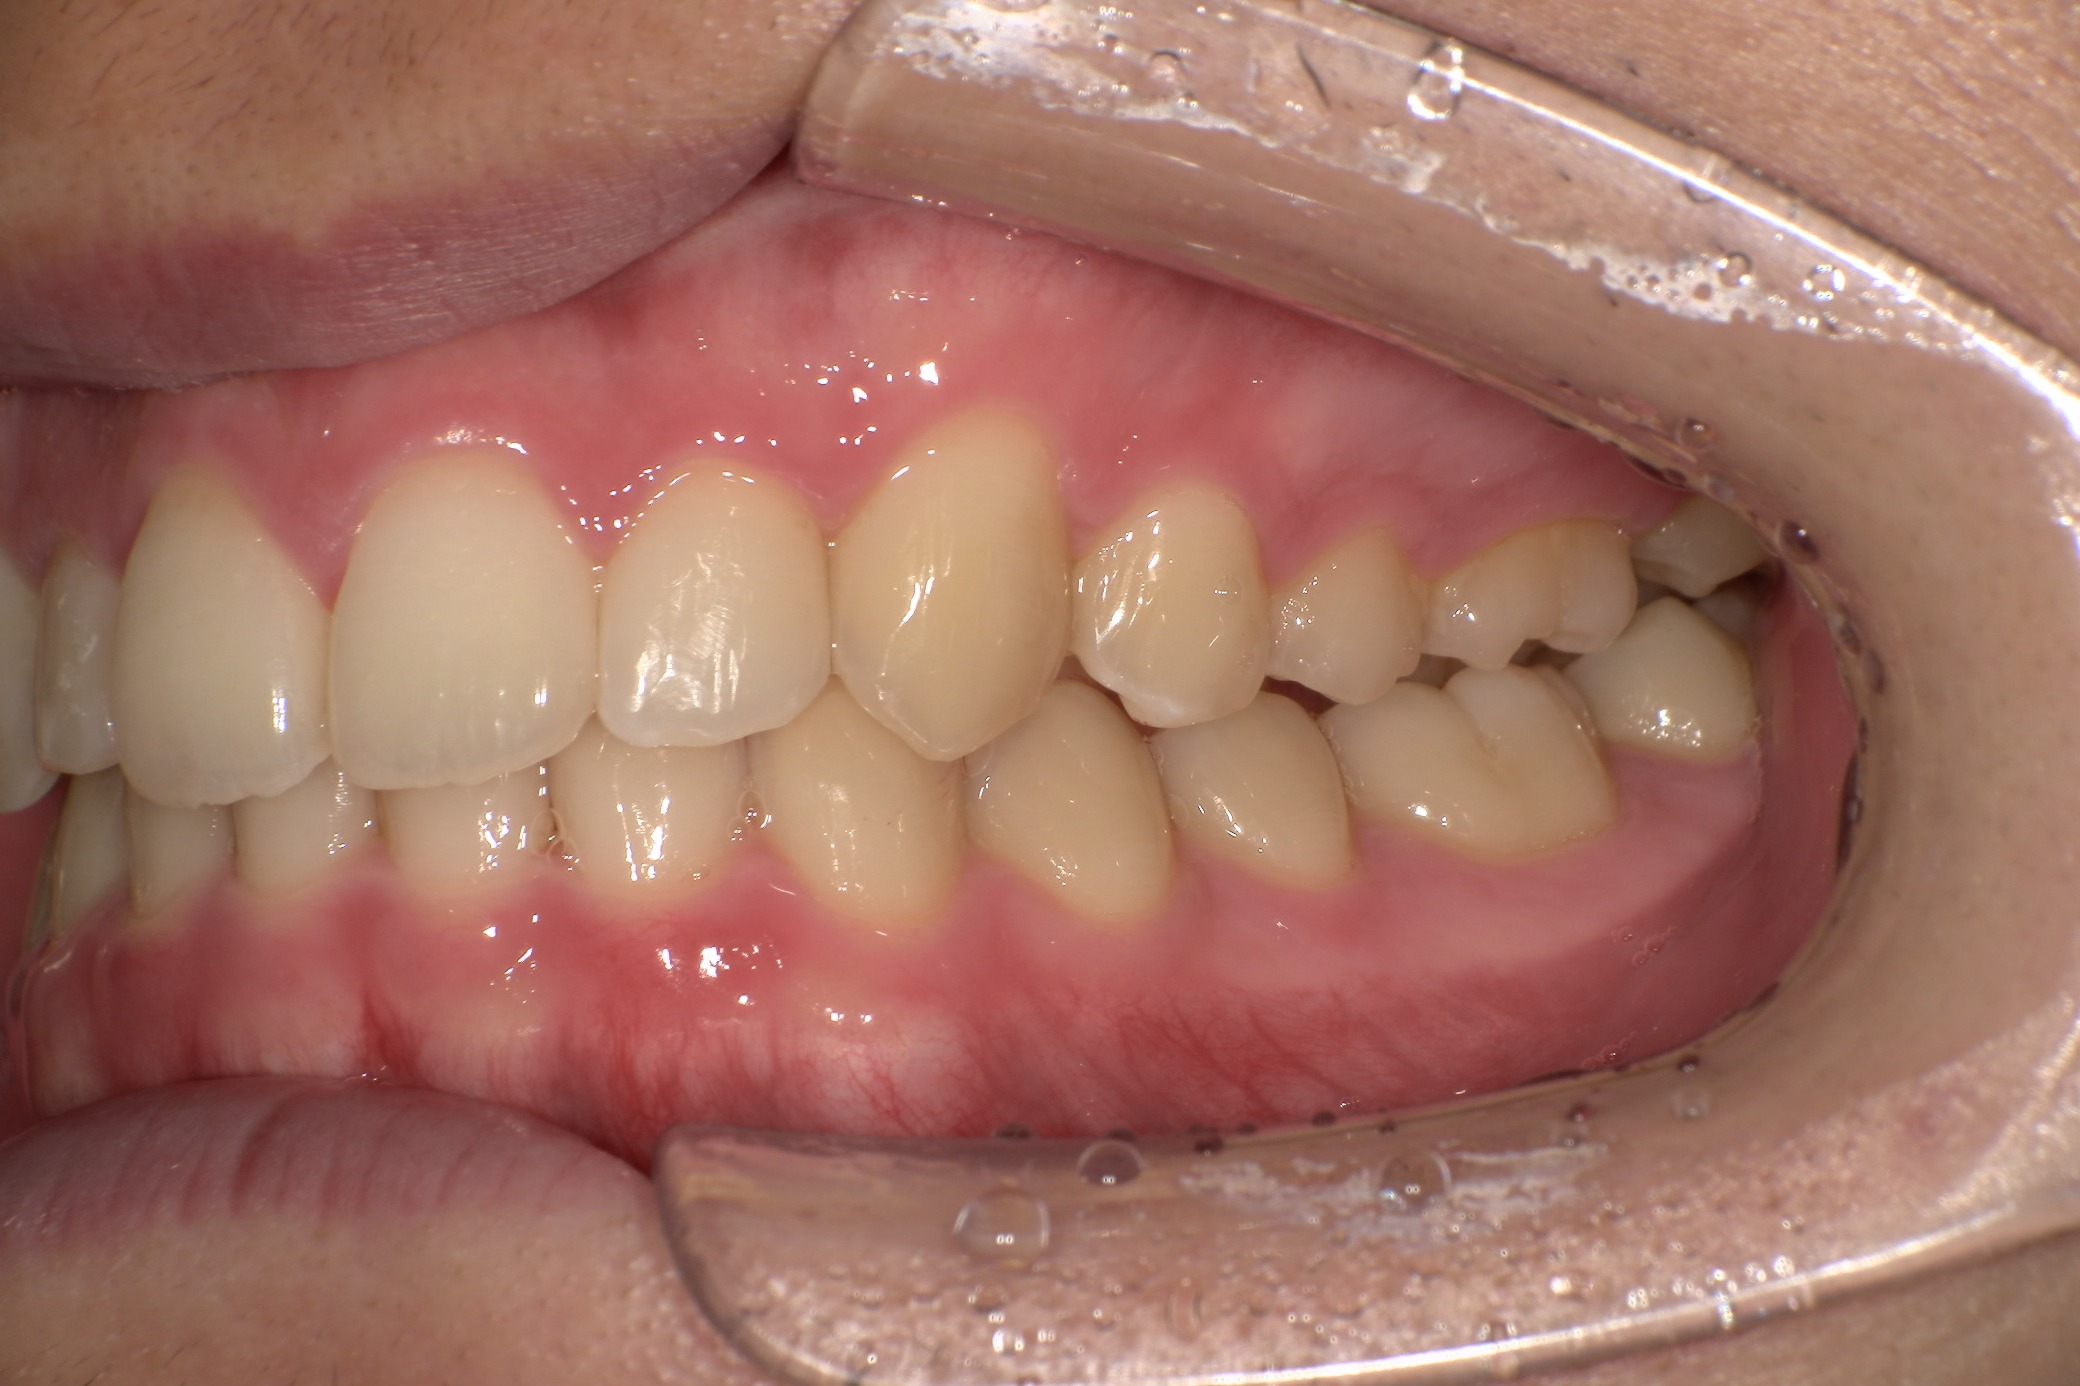

歯並びがコンプレックスで友人と写真を撮る際も気にしてしまっていたという20歳の男子大学生I.T.様にのI.T.様。始めやすい価格と目立ちにくさからスマイルモア矯正を選び、自信を持って笑えるようになった経緯を伺いました。

| 詳細情報 | |

|---|---|

| 費用 | 360,000円(税込396,000円) |

| 治療期間 | 6ヶ月 |

| 治療内容 | マウスピースを用いた歯列矯正 |

| 追加処置 | IPR |